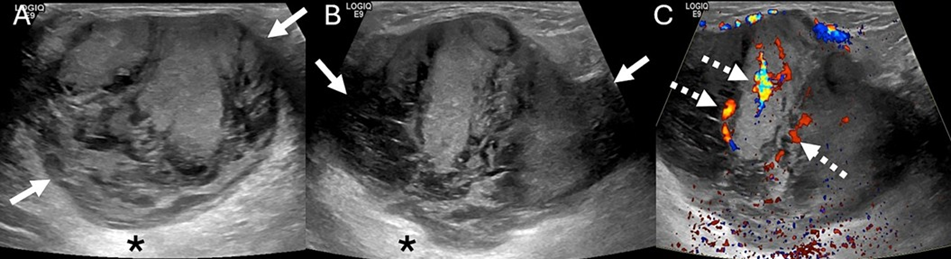

Figure 2: US images of a 77-year-old female with a palpable right breast mass in the lateral aspect of the right breast. Transverse (A) and longitudinal (B) US images of the right breast show an 8.0 cm, oval, parallel, heterogeneous mass (arrows) with indistinct margins and posterior acoustic enhancement (asterisk). Internal vascularity (dashed arrows) is present (C).

The mammogram showed an 8.2 cm, oval, high-density, non-calcified mass with predominantly circumscribed margins in the lateral aspect of the right breast (Figure 1). The left breast was normal. Targeted Ultrasound (US) of the right breast demonstrated an 8.0 cm, oval, parallel, heterogeneous mass with indistinct margins and posterior acoustic enhancement. Internal vascularity was present (Figures 2,3). The mass was assessed as a BI-RADS 4 lesion. US-guided biopsy of the mass was subsequently performed.

On mammography, PMC typically presents as an oval/round, equal to high-density mass with circumscribed or microlobulated margins [1,2,7]. Spiculated or indistinct margins are more indicative of MMC secondary to the IBC-NST component [1,2,7]. The ultrasound appearance of PMC is often as an oval/round mass with microlobulated or indistinct margins with variable echogenicity, ranging from isoechoic to mixed solid and cystic [1,2,7]. Posterior acoustic enhancement is often present due to high mucin content [1,2,7]. MRI features of PMC are of an oval/ round T1-hypointense, T2-hyperintense (due to mucin) mass often with rim or heterogenous enhancement [1,2,7,8]. Due to favorable histology, PMC is treated by surgical excision without nodal sampling [1]. Adjuvant endocrine therapy is recommended to decrease the risk of local recurrence and distant metastasis [1]. PMC has a low recurrence rate of 6.2% [1].